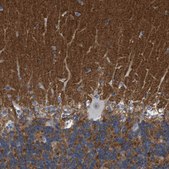

immunohistochemistry: 1:1000- 1:2500

The Human Protein Atlas project can be subdivided into three efforts: Human Tissue Atlas, Cancer Atlas, and Human Cell Atlas. The antibodies that have been generated in support of the Tissue and Cancer Atlas projects have been tested by immunohistochemistry against hundreds of normal and disease tissues and through the recent efforts of the Human Cell Atlas project, many have been characterized by immunofluorescence to map the human proteome not only at the tissue level but now at the subcellular level. These images and the collection of this vast data set can be viewed on the Human Protein Atlas (HPA) site by clicking on the Image Gallery link. We also provide Prestige Antibodies® protocols and other useful information.

- IHC tissue array of 44 normal human tissues and 20 of the most common cancer type tissues.